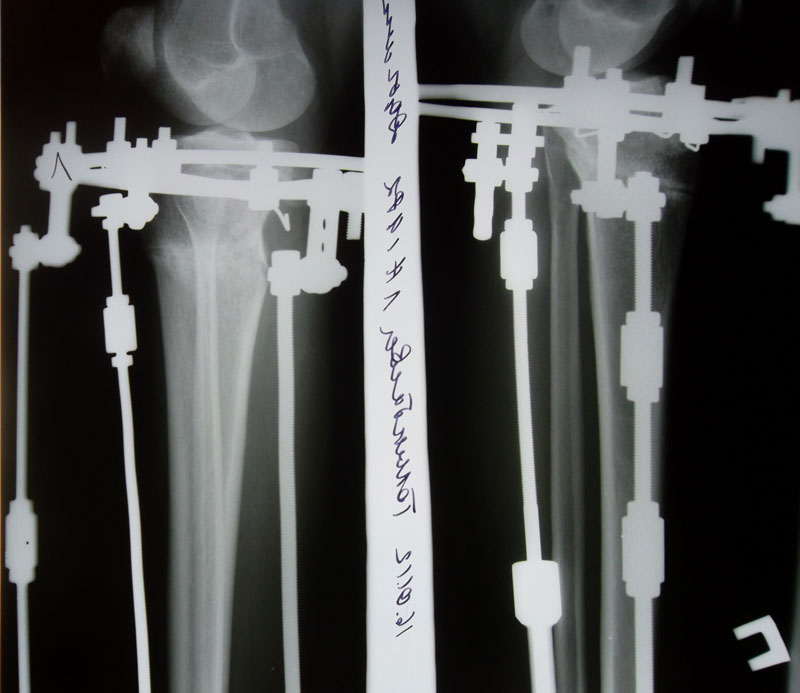

Пациентка Aylin, подарила себе новые ножки на 51-ом году.

19 января сняли аппараты.

Пациентка Solnyshko

Аппаратная жизнь 83 дня - закончилась. Сегодня сняли аппараты.